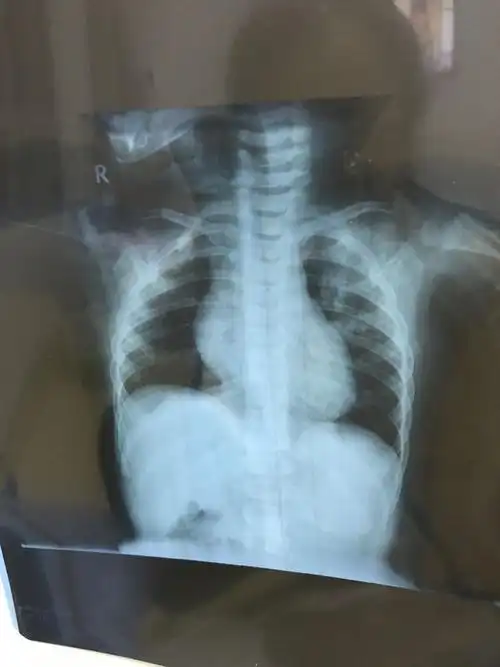

女童未及时就医诊断小儿支气管肺炎联合用药得以缓解

孩子3周岁多点,支气管肺炎入院治疗,6天后,孩子明显好转,医生依然让

儿童胸片 大家帮忙分析一下!